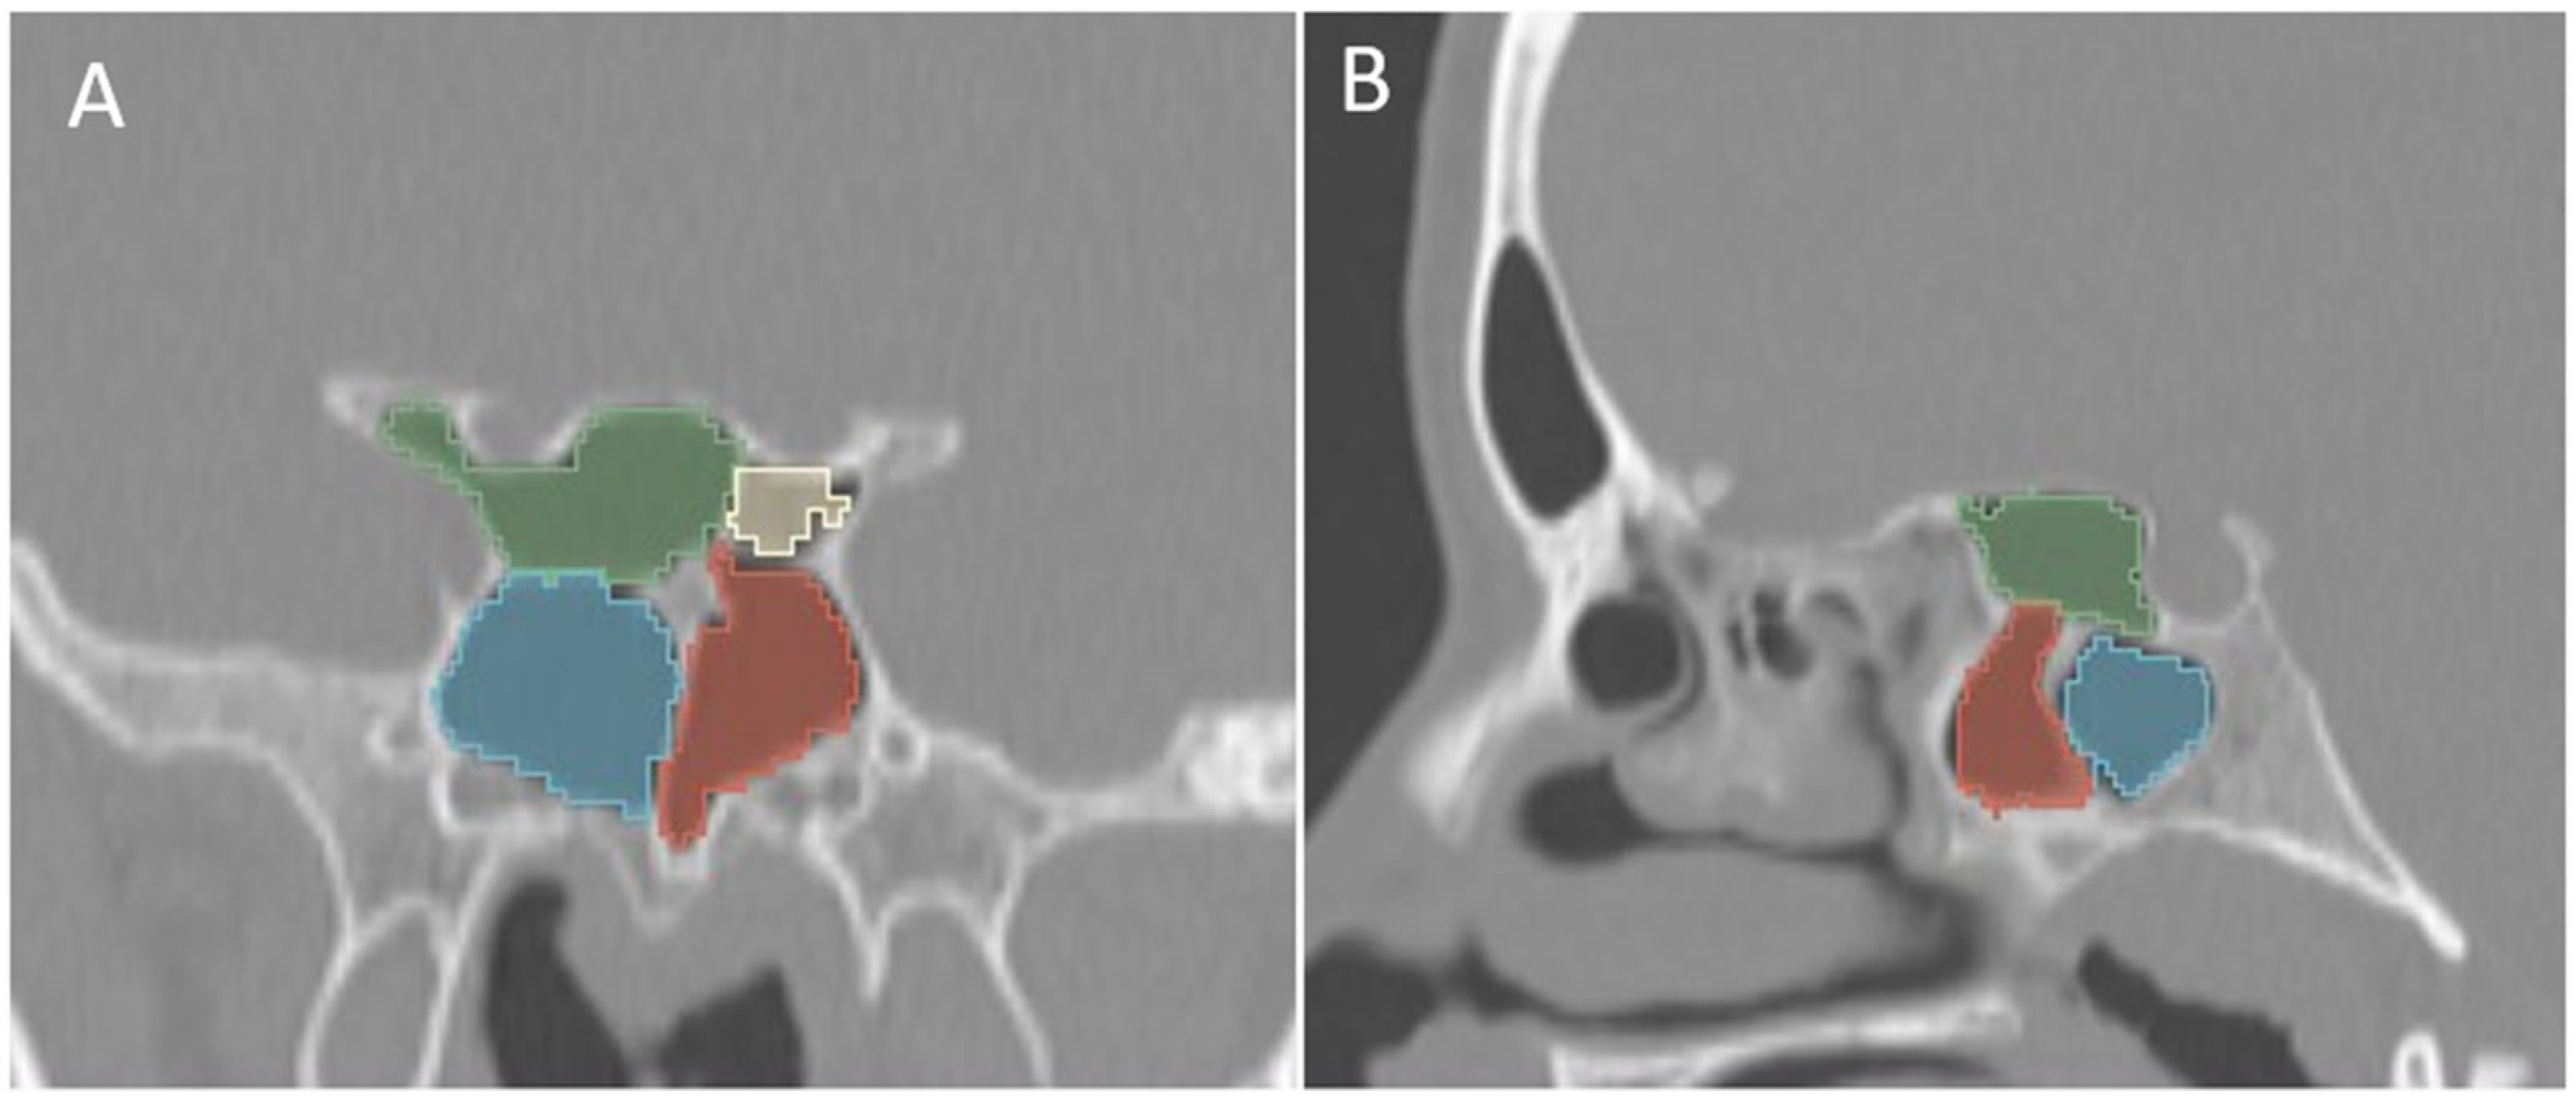

Additionally, the images were assessed for the presence of anatomic variants of the nasal cavity and PNS. Sinonasal variations were defined based on the European Position Paper on the Anatomical Terminology of the Internal Nose and Paranasal Sinuses [19]. According to this paper, the maxillary sinus is located between the orbital floor and alveolar process of the maxilla; the sphenoid sinus is the pneumatization of the sphenoid bone posterior to the rostrum; and the frontal sinus is defined as the pneumatization superior to a noticeable frontal beak [11,19]. The ANs are defined as the aeration of the protuberance on the lateral nasal wall, slightly anterior to the middle turbinate attachment (Figure 4). The Haller cell is an ethmoidal air cell, located below the orbital floor and lateral to a line parallel with the lamina papyracea (Figure 5). Onodi cell is the posteriorly located ethmoidal cell which develops just above and lateral to the sphenoid sinus (Figure 6). Concha bullosa is the pneumatization of the vertical segment of the middle turbinate (Figure 7) [19]. All anatomical variants were initially assessed by a single radiologist with four years of experience in maxillofacial CT imaging, who was blinded to patients’ demographic data, including age and sex. All assessments were done on a DICOM viewer (Medixant. RadiAnt DICOM Viewer [Software]. Version 2024.1. URL: https://www.radiantviewer.com (accessed on 1 November 2024)), after retrieval from the hospital PACS system to provide anonymized evaluation. The prevalence of each variant and the frequency of its bilaterality in each group were recorded. The evaluations were subsequently reviewed by a second radiologist with 11 years of experience. In cases of uncertainty regarding the presence of anatomical variations, a consensus decision was reached in consultation with a third radiologist with 13 years of experience.

Figure 6.

Coronal (A) and sagittal (B) reformatted CT images of a 13-year-old boy with bilateral Onodi cells (green and yellow) above the sphenoid sinuses (blue and red).